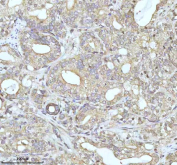

Immunohistochemical staining of MALSU1 using anti-MALSU1 antibody. MALSU1 was detected in a paraffin-embedded section of human prostate adenocarcinoma tissue. Heat mediated antigen retrieval was performed in EDTA buffer (pH 8.0, epitope retrieval solution). The tissue section was blocked with 10% goat serum. The tissue section was then incubated with 2 ug/ml rabbit anti-MALSU1 antibody overnight at 4oC. Peroxidase Conjugated Goat Anti-rabbit IgG was used as secondary antibody and incubated for 30 minutes at 37oC. The tissue section was developed using an HRP secondary and DAB substrate.